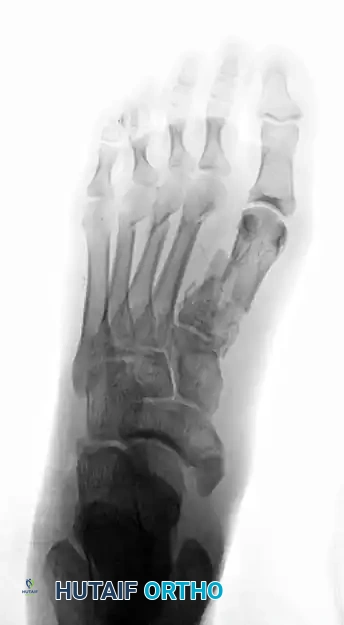

When faced with a displaced first metatarsal fracture combined with fractures of the lesser metatarsals and associated joint subluxations/dislocations, the surgical priority is to restore the medial column (the first ray) first.

Preoperative anteroposterior radiograph demonstrating a high-energy crush injury with a displaced first metatarsal fracture and comminuted fractures of the second to fourth metatarsals, disrupting the entire forefoot cascade.

Preoperative lateral radiograph of the same injury, highlighting the severe dorsal displacement and instability of the metatarsal segments.

- First Ray Stabilization: The first metatarsal is the primary weight-bearing axis of the forefoot. It must be anatomically reduced and rigidly fixed. Open reduction and internal fixation (ORIF) using a low-profile titanium plate and screws is the gold standard.

- Lesser Ray Stabilization: Once the first ray is restored to its anatomic length and rotation, the lesser metatarsals are addressed. Because of the comminution and the need to minimize soft tissue stripping in crush injuries, closed reduction and percutaneous pinning (CRPP) with stout Steinmann pins or K-wires is often preferred over formal plating for the lesser rays.

Postoperative anteroposterior radiograph showing anatomic restoration of the forefoot. The first metatarsal has been rigidly stabilized with plate and screw fixation, while the lesser metatarsals have been aligned using percutaneous Steinmann pins.

Postoperative lateral radiograph confirming the restoration of the sagittal alignment of the metatarsals and the reduction of the associated joint spaces.